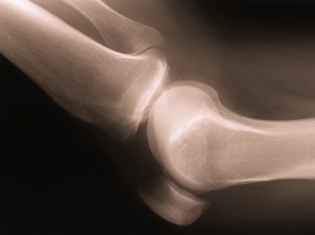

(RxWiki News) Metabolic syndrome is the name for a group of factors that boost the risk of heart disease and diabetes. Now, it seems metabolic syndrome may also be linked to the "wear-and-tear" of arthritis.

People with just one risk factor of metabolic syndrome - such as being overweight or having high blood pressure - may have an increased risk of knee osteoarthritis.